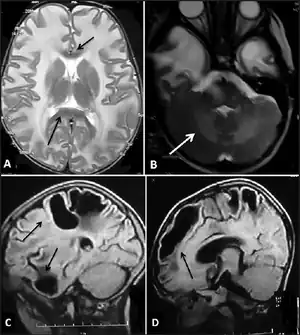

| Megalencephalic leukoencephalopathy with subcortical cysts- a) Bilateral confluent symmetrical diffuse white matter involvement arrow (b) and cerebellar white matter involvement arrow c,d) subcortical cysts in temporal, frontal,parietal areas arrow | |